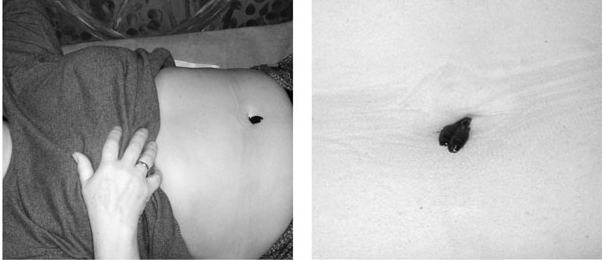

Постановка пиявки пациенту в пупок

Постановка пиявки пациенту в пупок

Постановка пиявки пациенту в пупок

Постановка пиявки пациенту в пупокЕсли пиявка поела хоть наполовину – ее легко снять, погладив сухим ватным диском по мордочке. Если совсем маленькая, придется намочить диск в водке или спирте и поднести к ее носику – она тут же плюнет и примется бежать. Не надо обжигать спиртом ее мордочку – эффект и так всегда есть. Все, пиявку в отдельную банку, а на укус положить кусочек прокладки и наклеить липкий бинт. Он так и называется: «Бинт-Ли». Берите в аптеке отечественный – он в три раза дешевле импортного, но нисколько не хуже. Обычными пластырями я не пользуюсь, они травмируют кожу. Если ваш пациент мужчина и вокруг пупка волосы – прибинтуйте прокладку эластичным бинтом, только не затягивайте туго, не мешайте процессу истечения крови. Если волос нет – фиксируйте «Бинт-Ли». Через 4–6 часов проверьте место укуса – если кровь перестала течь, промойте его чистой водой и смажьте любым противоаллергическим кремом, чтобы не чесалось. Подойдут «Гистан», «Боро-плюс», «Звездочка» и другие. Если не перестала – смените прокладку и ложитесь спать. Хоть и говорят, что теоретически кровь может подтекать до двух суток, на практике я такого за 10 лет не видела ни разу. Лишь дважды кровь текла около суток, а обычно уже через 4–8 часов все прекращается. Если идет 12 часов – прекрасно. Это лучше, чем два. Значит, кровь не такая уж вязкая, ответ на слюну пиявки хороший, меньше скопится грязи около укуса и не будет чесаться, больше заменится крови – чище станет общий кровоток. Так что не пользуемся никакими медицинскими клеями и перекисями водорода – пусть процесс продолжается как можно дольше.